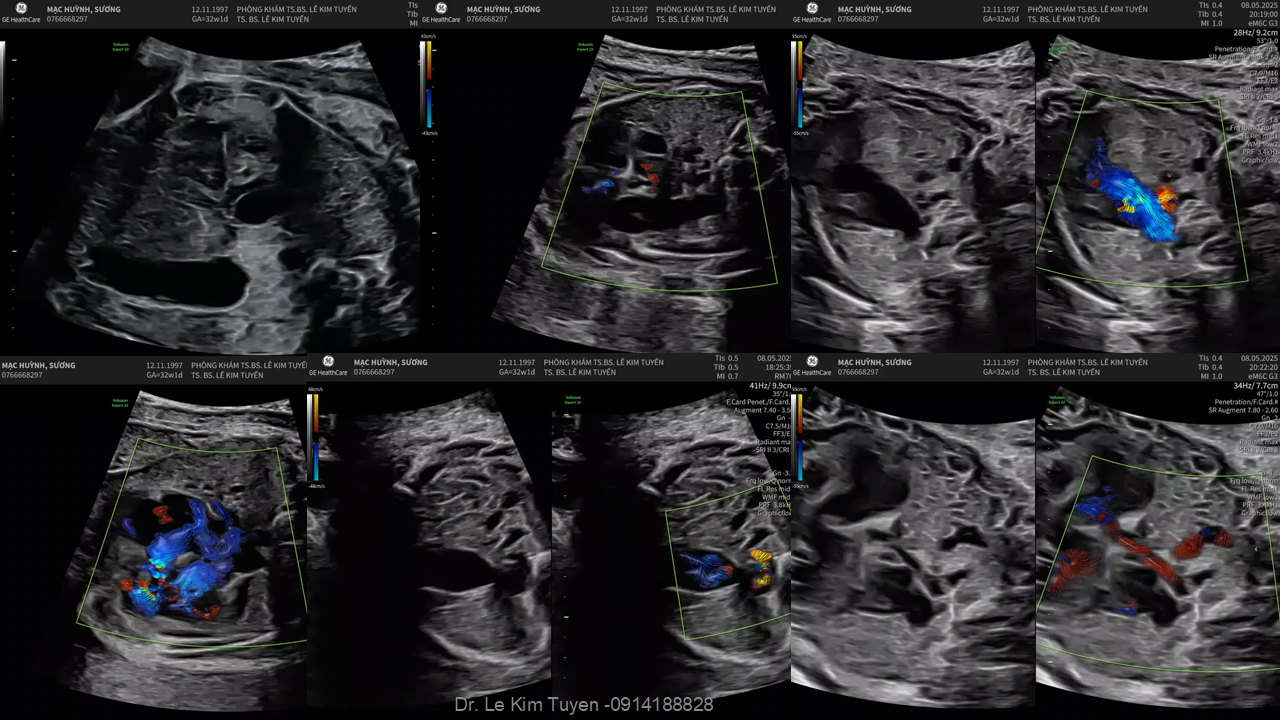

Áp dụng công nghệ Graphicflow trong phát hiện bệnh tim bẩm sinh cần cấp cứu sơ sinh

TS. BS. Lê Kim Tuyến

Bệnh viện Tim Tâm Đức